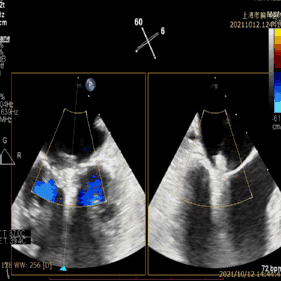

术前超声评估:

术前TEE提示重度功能性二尖瓣反流,反流位于A2/P2;

前瓣长度:20mm;后瓣长度:11mm;

前、后瓣叶对合深度:8mm;对合长度3mm;

瓣叶及瓣环无钙化,二尖瓣有效开口面积4.4cm2。

图1:术前TEE提示二尖瓣重度反流,反流位置位于A2/P2区